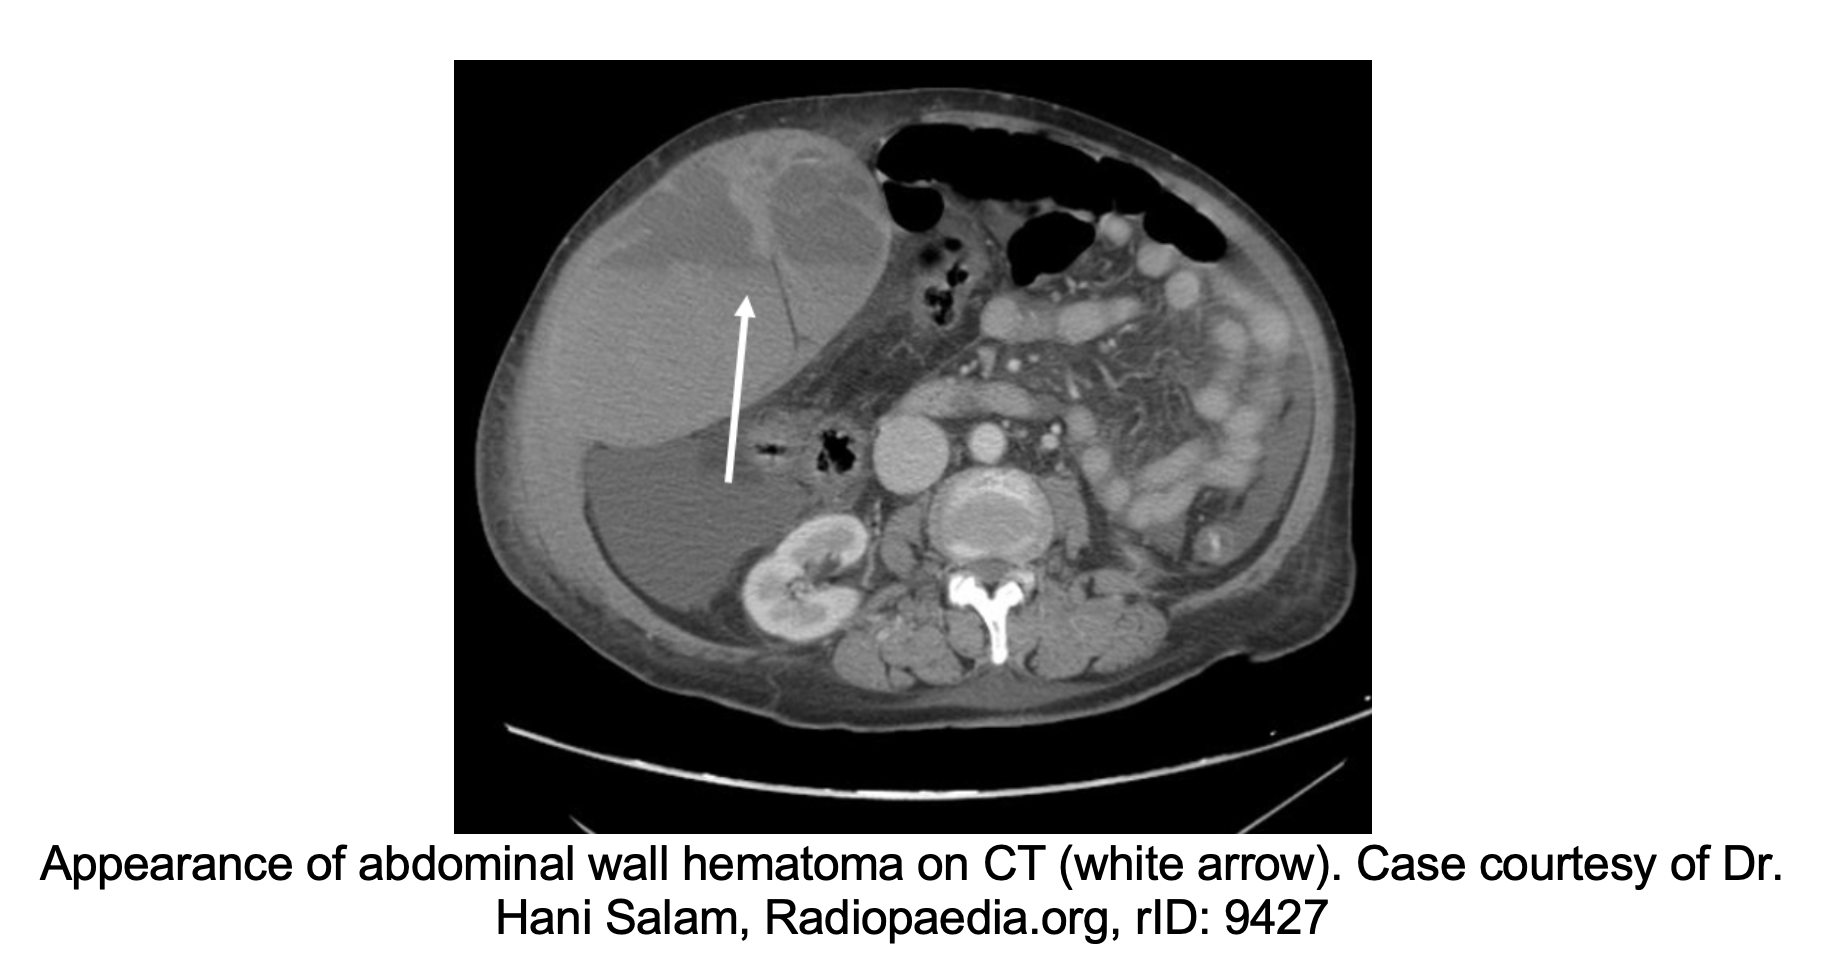

In the post-operative period, patients who present with any vital sign abnormalities warrant further investigation for a source of bleeding. In addition to obtaining a complete blood cell count to look at any hemoglobin and hematocrit changes, an ultrasound can be helpful in identifying heterogeneous fluid collections and especially hematomas. If the ultrasound is equivocal, a contrasted computed tomography can be helpful in identifying the location of a hematoma, if present, or areas of active extravasation.26